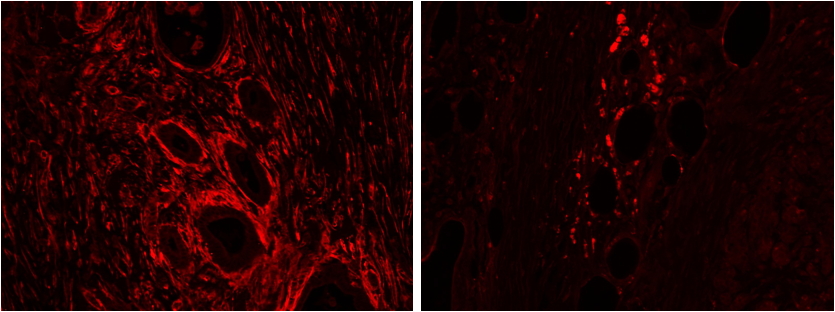

AMM05013G (2 μg/ml) staining of paraffin embedded Human Pancreas: cancer (left), adjacent to cancer (right). Steamed antigen retrieval with citrate buffer pH 6, Alexa594-staining.